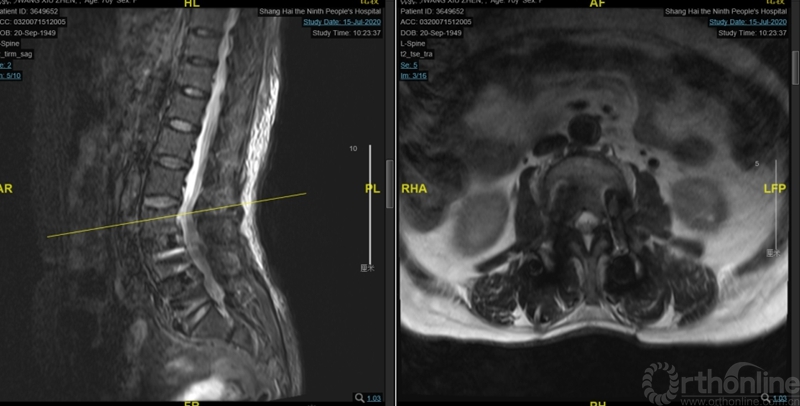

图3:术前核磁:腰3-4、4-5椎管狭窄

术后麻醉清醒后出现急性腰椎管狭窄症状:双足屈伸活动无力伴有麻木,以术前对侧无症状侧的左侧肢体为重。核磁显示:近端减压交界区硬膜囊成角和卡压,硬膜囊向右侧椎管减压侧漂移(图6、7)。

图6:第一次术后核磁:近端减压交界区硬膜囊成角卡压

图7:术后核磁:硬膜囊右侧减压侧椎管漂移